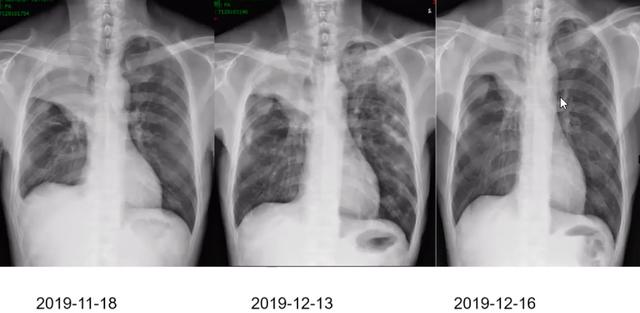

-2019-10-25、11-14 予第1、2周期白蛋白结合型紫杉醇+卡铂+帕博利珠单抗治疗

2019-12-11 CT:考虑右肺上叶肺癌并双肺、胸膜多发转移。左肺上叶癌性淋巴管炎

CEA:122.07 ng/mL,非小细胞肺癌相关抗原:11.38 ng/mL-12-12 第3周期白蛋白紫杉醇+卡铂(未使用免疫治疗),甲强龙 60mg qd

12-16 复查胸片:肺部病变较前吸收

讨论点

1 肺部阴影病因:1.免疫相关肺炎?2.肺部感染?3.肺转移癌

2 患者目前疗效评价?

3 下一步治疗?

点评

1 该患者虽然影像资料与平时常见的免疫相关肺炎表现有所差别,但在第3周期治疗后病灶在4天内短时间内缩小,不排除免疫相关肺炎可能,可以继续原方案化疗。

2 建议再次进行PET-CT,与前次比较,再决定下一步治疗策略。